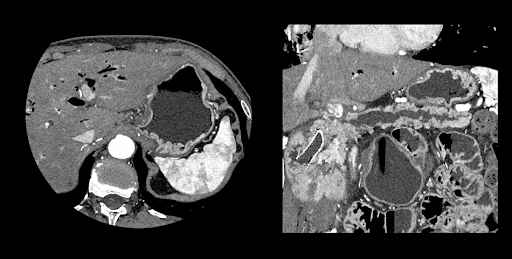

Визуализация органов грудной полости, живота и малого таза